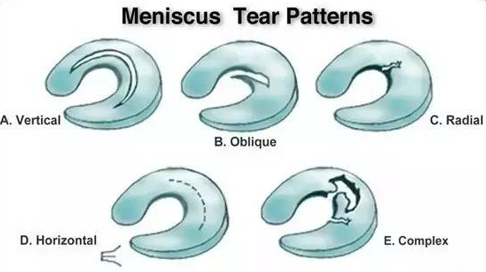

【半月板损伤的分类】

半月板损伤类型的示例

5大类半月板损伤的类型